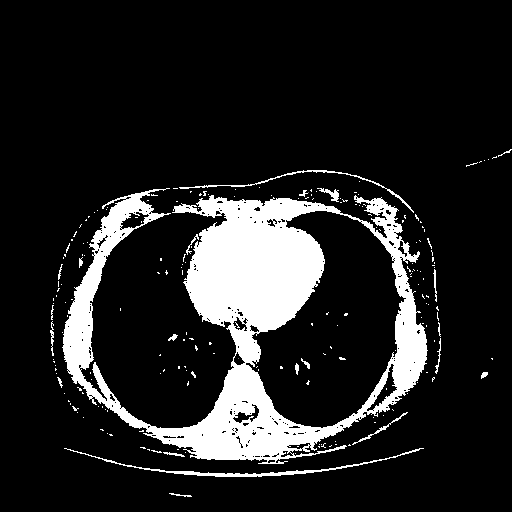

Generated VENOUS CT scan (A→B translation)

Full window (WL 1023.5, WW 4095 β†’ Low βˆ’1024, High +3071)

Actual HU range: [-1024.0, 3071.0]